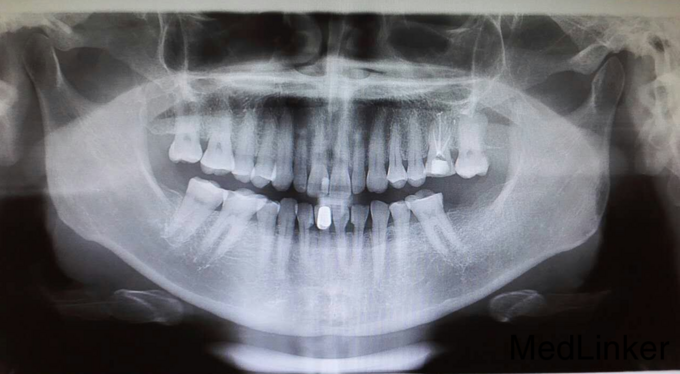

患者女45岁后牙缺失 欲种植

后牙缺失 欲种植